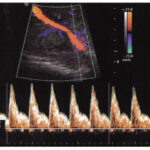

Imágenes

En LATIVA, nos especializamos en diagnósticos precisos y manejo integral para la salud de la madre y el bebé. Nuestro equipo de subespecialistas certificados utiliza tecnología de vanguardia para ofrecerles tranquilidad y el mejor cuidado posible en cada etapa.